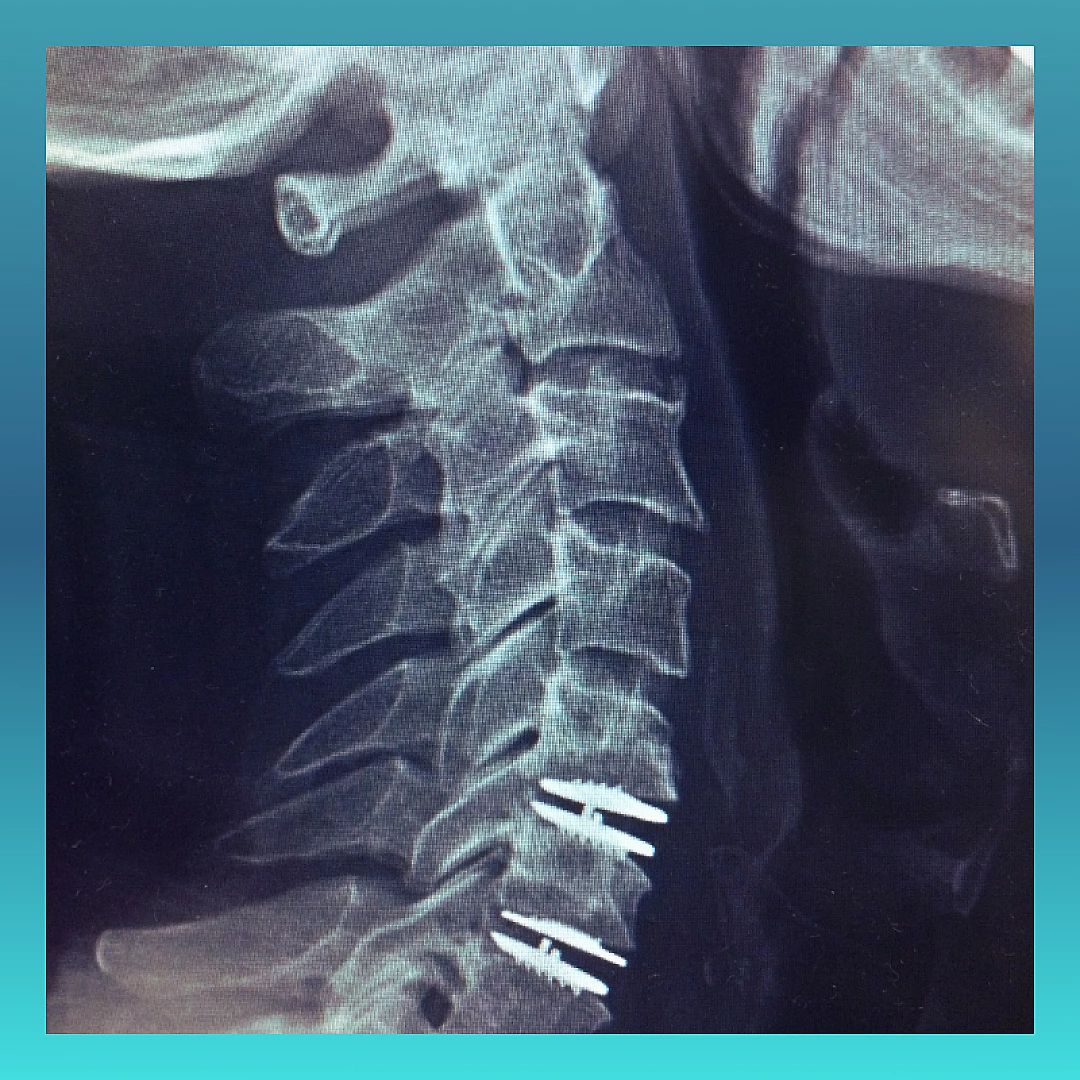

استبدال الديسك العنقي الاصطناعي

جراحة استبدال الديسك العنقي تنطوي على إزالة الديسك العنقي المصاب واستبداله بديسك اصطناعي

عندما يضيق المسافة بين فقرات عنق الرحم، قد يؤدي ذلك إلى دفع جزء من فقرات العنق الرحم إلى الحبل الشوكي، مما يسبب الألم والخدر والضعف. وعندما تفشل العلاجات غير الجراحية في تخفيف هذه الأعراض، قد يكون هناك حاجة لإجراء جراحة استبدال الديسك الاصطناعي.